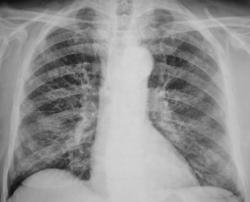

Иллюстрации 5, 6. Справа аналогичные изменения в ребрах и лопатке.

Предположительно выставлен диагноз метастазирования из первичного узла, расположенного в предстательной железе.